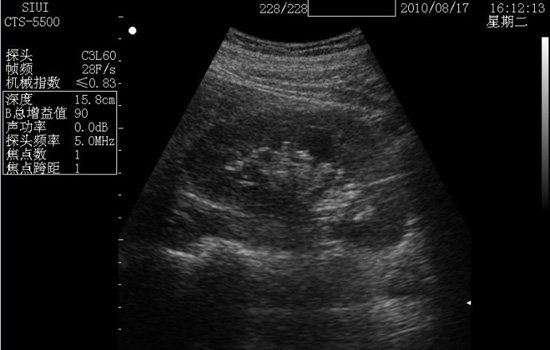

普通B超

普通b超其实也就是二维的黑白b超。普通b超的应用范围也很广,主要是作用就是观察身体内部结构,比如孕妇胎儿情况、肝脏等部位。用孕妇b超检查来说,普通b超是黑白色的,通过b超测出胎儿双顶径、头围和腹围等数据,进一步确认宝宝的预产期,还可帮助医生观察胎儿是否存活或有无畸形,羊水是否过多等。

价格:普通B超价格相对比较便宜,不同地方的医院价格会不一样,但差异基本相差不大,最便宜的有35元,稍贵一点的90元也有。